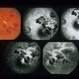

- branch vein occlusion (BVO)